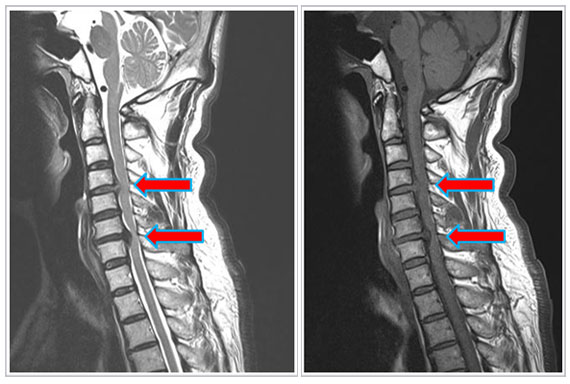

* Áø´Ü

»ó±âÇÑ Áõ»ó°ú ÇÔ²² ÆÈÀ̳ª ¼ÕÀÇ ±Ù·Â ¾àÈ,

°¨°¢ ÀúÇÏ ¶Ç´Â Àú¸°°¨ÀÌ ÀÖÀ¸¸é ¸ñ µð½ºÅ©¸¦

ÀǽÉÇÒ ¼ö ÀÖÀ¸¸ç °Ë»ç ¹æ¹ýÀ¸·Î´Â ÀϹÝ

x-ray, CTµîÀÌ µµ¿òÀÌ µÇ³ª °¡Àå Á¤È®ÇÑ °Ë»ç ¹æ¹ýÀº

MRI Áï ÀÚ±â°ø¸í¿µ»ó °Ë»ç ÀÔ´Ï´Ù.